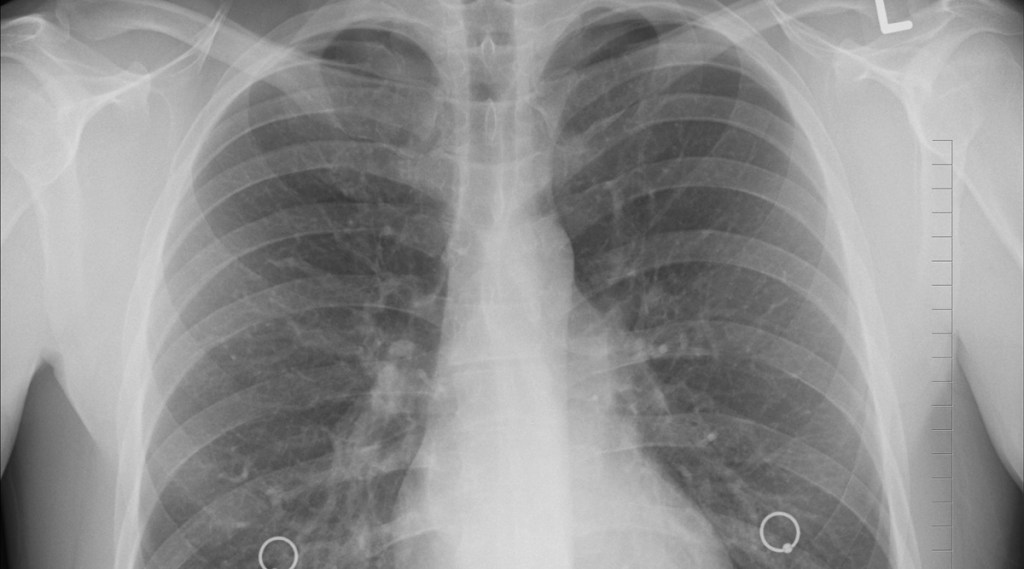

Chronic Obstructive Pulmonary Disease (COPD) is a group of inflammatory diseases that obstruct airflow from the lungs and make breathing difficult. COPD is now the second leading cause of death in India, after heart disease. According to the Global Burden of disease study 2018, COPD claimed almost 1 million lives in India in 2017. Progressive conditions like chronic bronchitis, emphysema, refractory asthma contribute most to the COPD burden. Long term exposure to tobacco, indoor or outdoor air pollution and particulate matter is associated with the development of this disease. Unfortunately, COPD is an incurable condition whichworsens over time and symptoms include difficulty in breathing, excess mucus production, and wheezing.

There is no permanent cure for COPD. Once damage is done to the lungs, it is permanent. It results in shortness of breath and difficulty breathing. But, treatment and following certain precautions can ease symptoms, prevent complications, and generally slow disease progression.